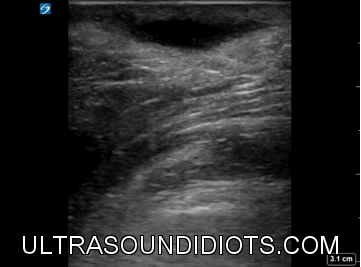

Soft Tissue Abscess